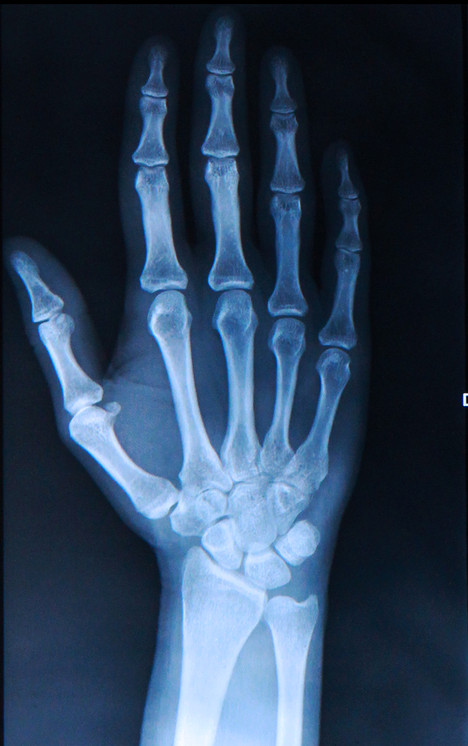

La condromatosi viene diagnosticata dallo specialista tramite radiografia o biopsia.